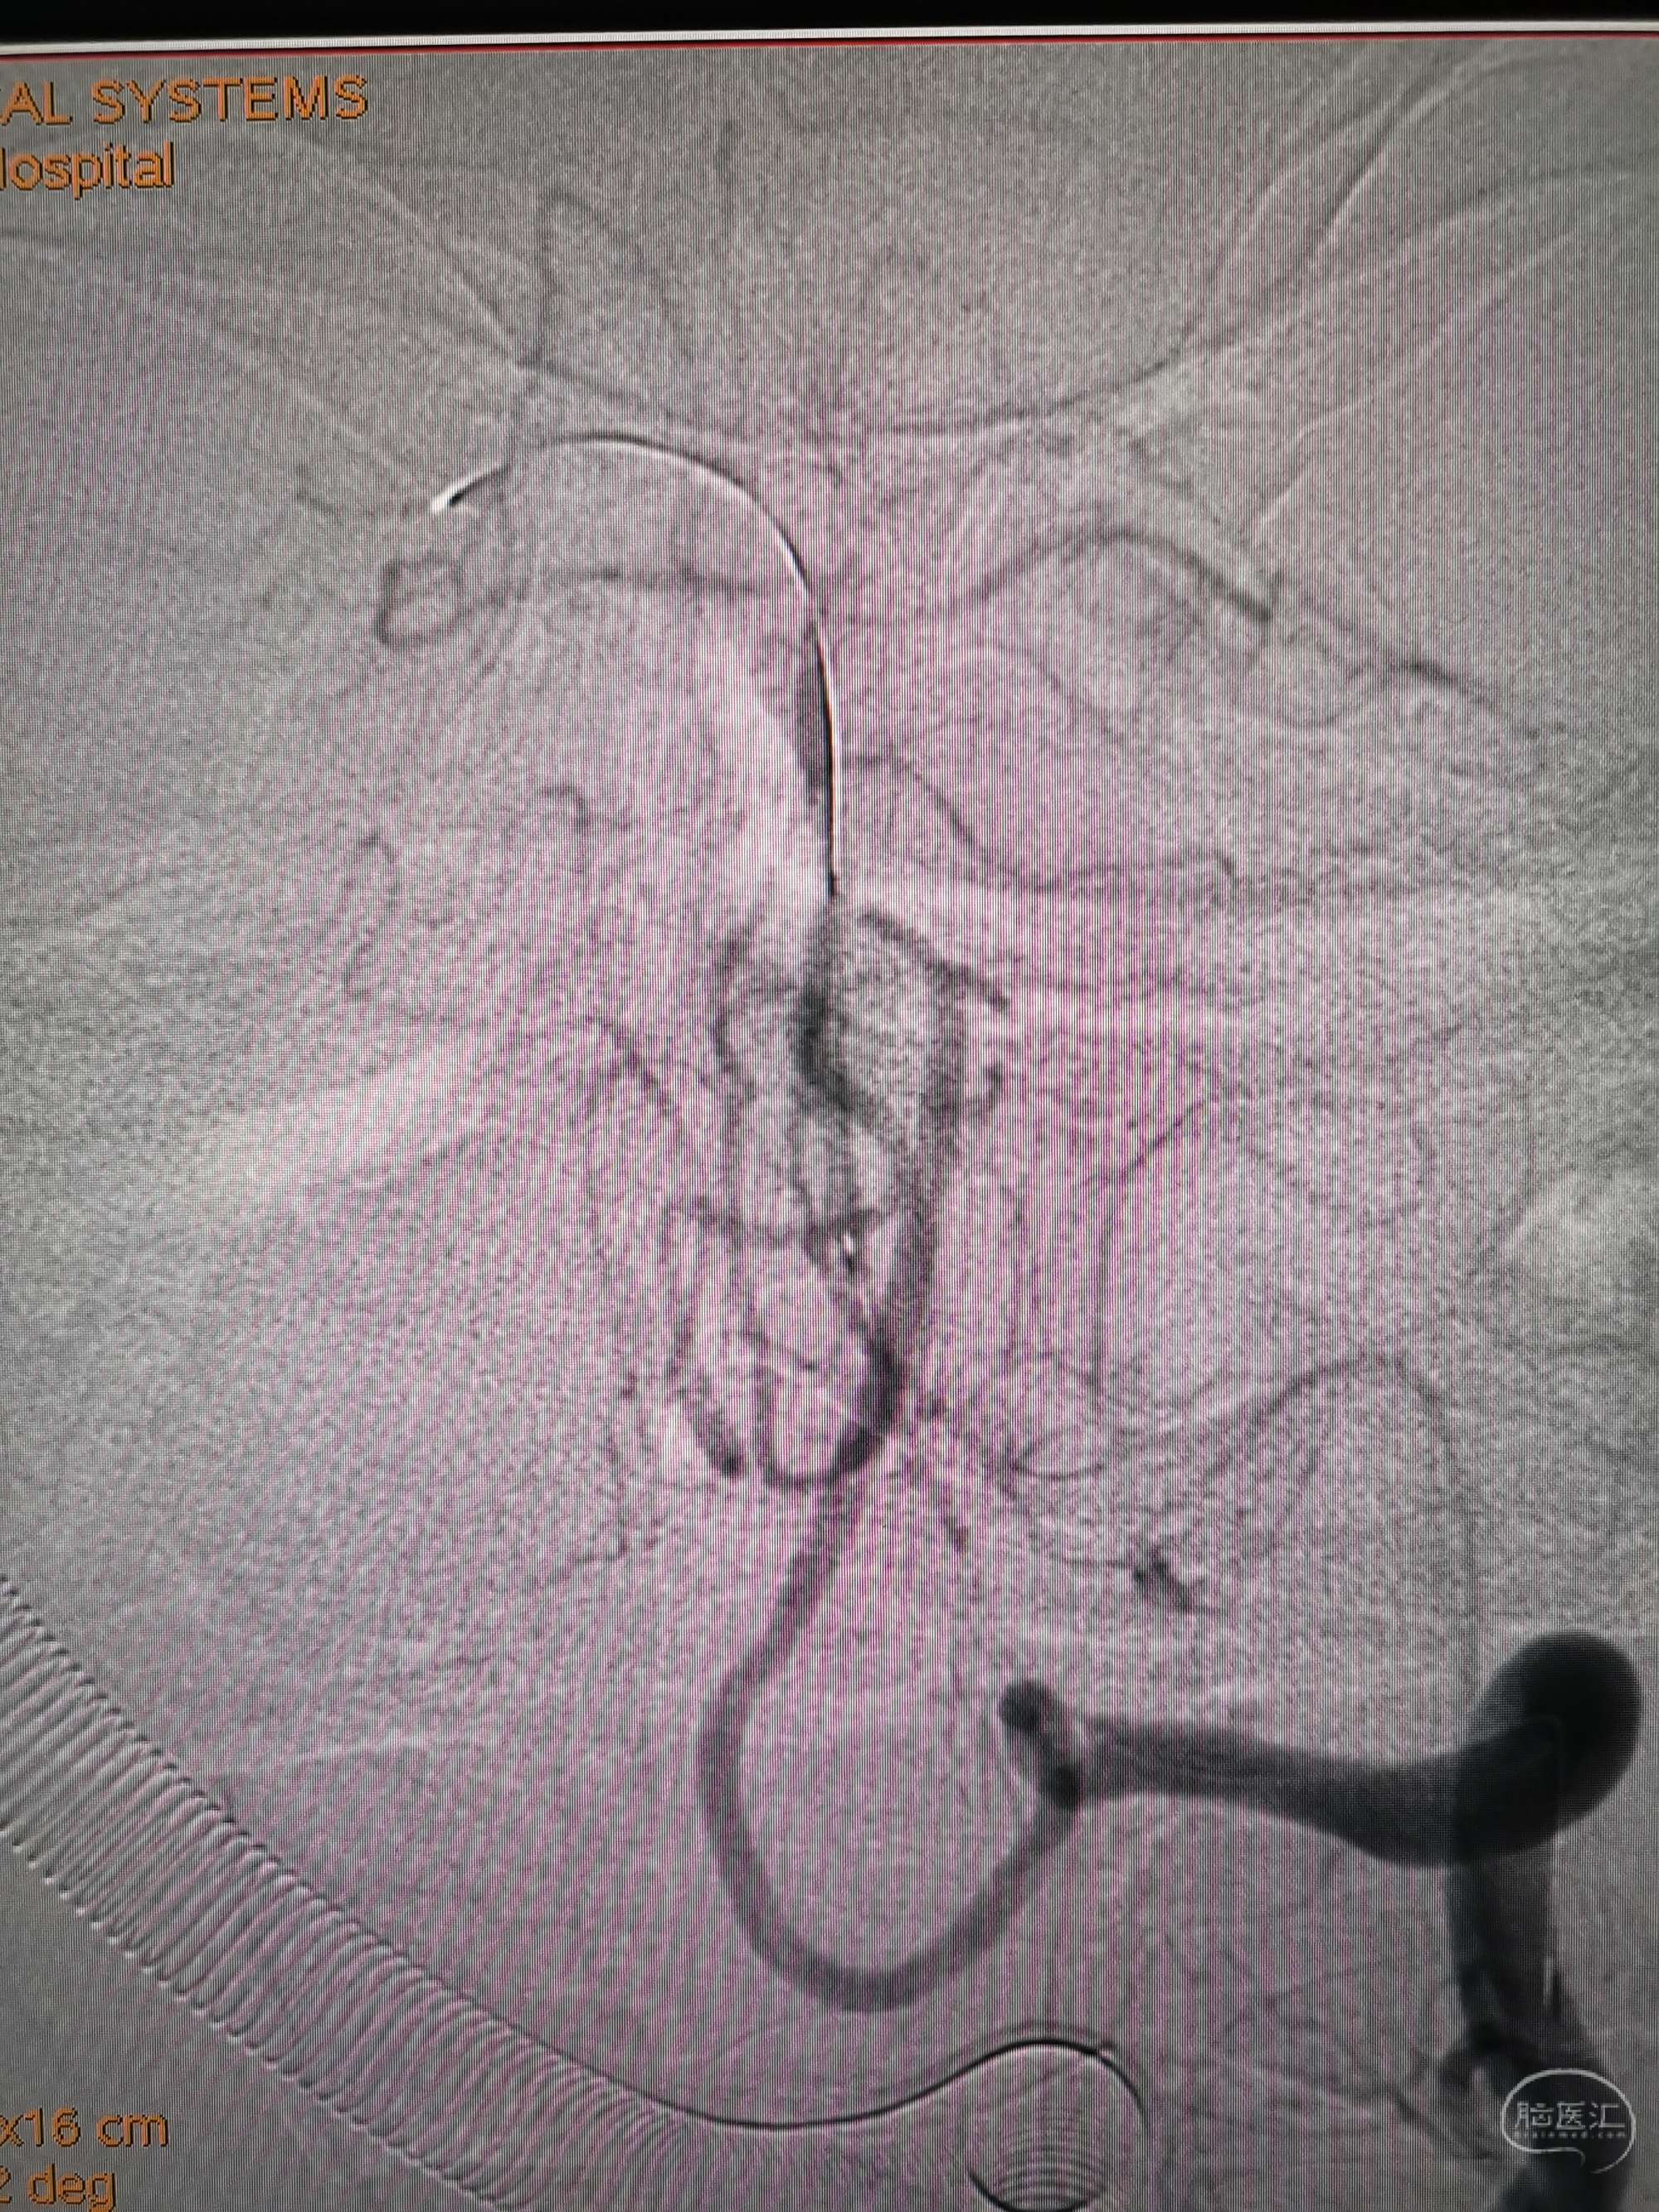

术前再次造影评估

右侧椎动脉穿支供血及左侧PICA供血较入院时略有改善,但改善不明显。故按计划行左侧椎动脉再通术